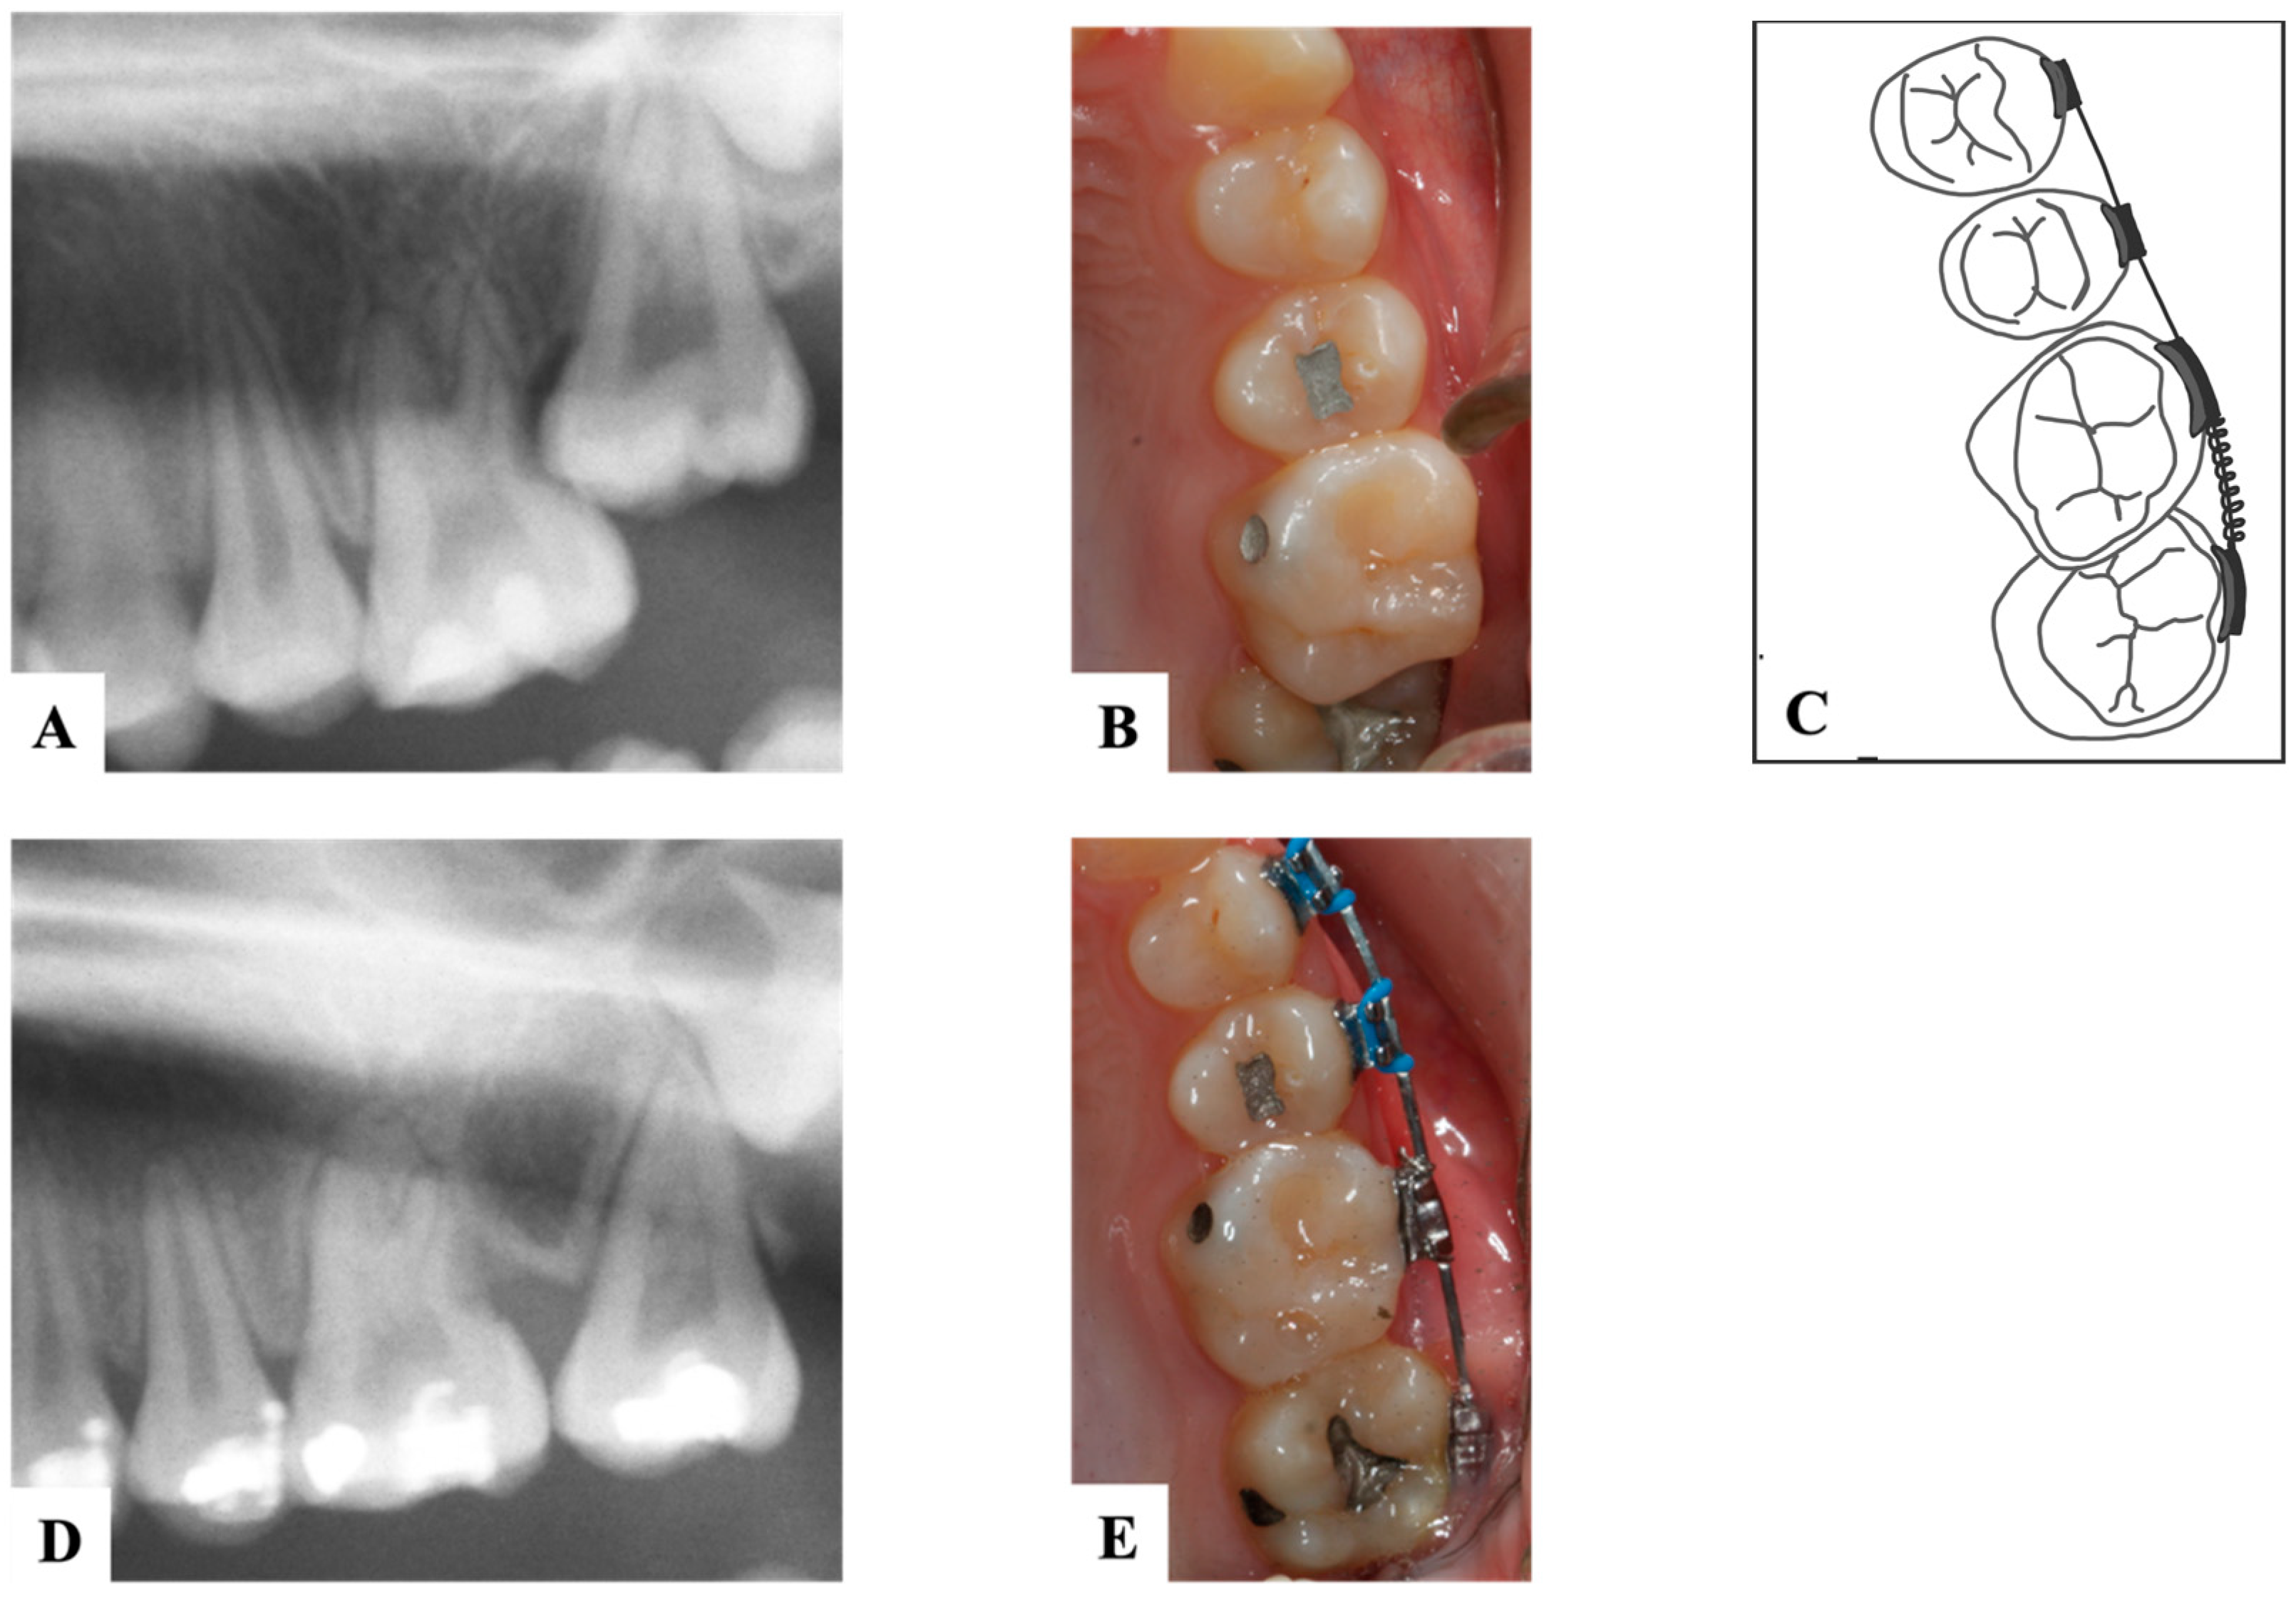

9. Ectopic First Permanent Molars

9.1. Interproximal Wedging

9.2. Distal Tipping

10. Ectopic Second Permanent Molars

11. Novel Devices